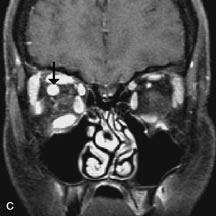

Pleomorphic adenomas demonstrate long T1 and T2 signal characteristics. They may show heterogeneity on T2-weighted images74 and moderate to marked enhancement with contrast.75 Signal characteristics of adenoid cystic carcinoma include hypointensity to fat on T1-weighted images, hyperintensity to fat with increased T2 weighting, and isointensity to fat on proton density-weighted studies (Fig. 23).31,75 Secondary bony alterations of the lacrimal fossa associated with lacrimal gland tumors, such as remodeling (benign mixed tumor) or destruction (adenoid cystic carcinoma), are seen indirectly on MR images; however, bone windows on CT scans provide better delineation of these changes. In contrast to the round or globular appearance of benign or malignant epithelial tumors of the lacrimal gland, lymphoproliferative tumors usually appear to be molding or draping onto the globe and the surrounding bony orbit.

Fig. 23. A. T2-weighted and (B and C) postcontrast fat-suppressed T1-weighted MR scans demonstrate an infiltrative lacrimal region mass than invades the lateral rectus muscle (arrows). This highly cellular lesion is seen to have a very hypointense appearance on the T2-weighted scan.